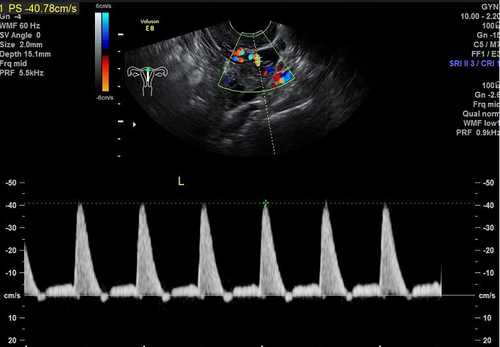

子宫动脉血流减少提示子宫动脉阻力高,一般见于高血压、高血脂以及自身免疫性疾病合并妊娠的患者。子宫动脉是为胎儿提供营养,进行母婴之间的血液循环,提供氧气等营养物质,排出二氧化碳等代谢废物的通路。如果出现了子宫动脉血流慢,容易导致出现子宫发育缓慢,导致子宫内膜的发育异常,从而导致出现不孕、流产,胎儿发育异常。